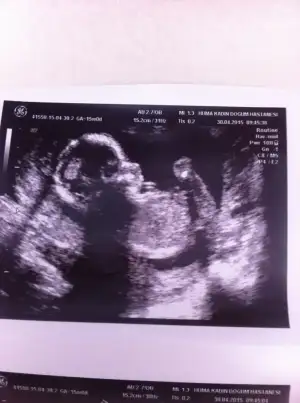

mrb arkadaşlar bugün 15 haftalık olduk kontrol vardı ve cinsiyetimize %51 den yüksek erkek dedi. resimler kalitesiz diyende var siz anlayabilirmisiniz merak beni öldürecek :)